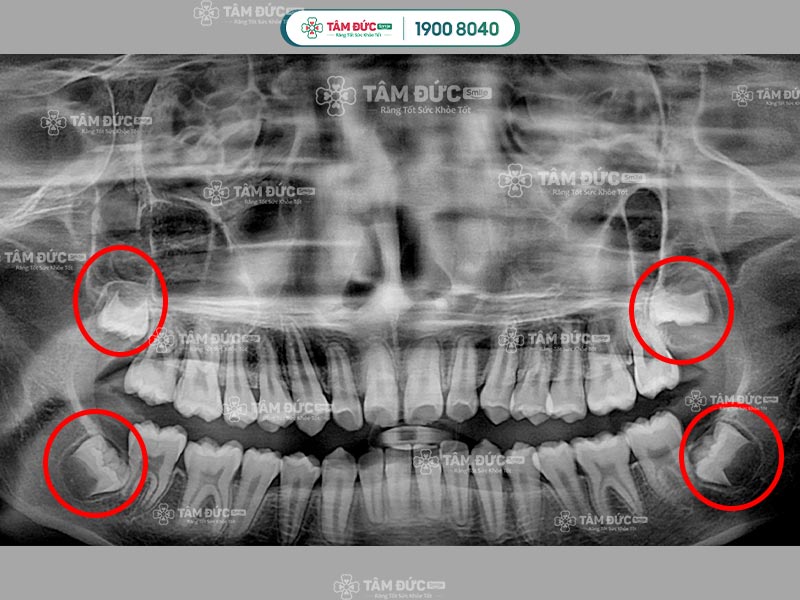

Trên cung hàm, răng khôn là chiếc răng số 8, mọc sát vách hàm và nằm ở trong cùng hàm răng. Răng khôn mọc sát răng số 7, Quý khách sẽ có 4 chiếc răng khôn chia đều cho cả hàm trên và dưới.

Răng số 8 sẽ gây đau trong các trường hợp mọc ngầm, mọc lệch, mọc đâm vào răng số 7,... Mặt khác, sự phát triển của răng khôn cũng làm cho bề mặt nướu bị phá vỡ, từ đó gây đau nhức dai dẳng. Sở dĩ mọc răng khôn gây đau vì lúc này xương hàm đã phát triển hoàn thiện, không đủ chỗ cho răng khôn mọc lên.